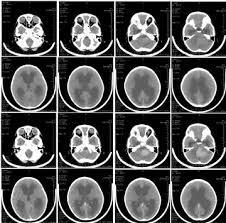

Brain Tumor Cancer Childhood - Childhood Cancer Death Rates Continue To Fall Cdc : Signs and symptoms treatment resources for families find a doctor clinical.. Signs and symptoms treatment resources for families find a doctor clinical. Brain tumors can occur in both children and adults. A brain tumor epidemiology consortium review. And they are less common in children than adults. This pdq cancer information summary has current information about the treatment of childhood brain and spinal cord tumors.

If cancer spreads to the meninges and the cerebrospinal fluid. This pdq cancer information summary has current information about the treatment of childhood brain and spinal cord tumors. Secondary (metastatic) brain tumors are tumors that result from cancer that starts elsewhere in your body and. However, these cases are only a small. Learn about the diagnosis & treatment here. A cancerous tumour is a group of cancer cells that can grow into and destroy nearby tissue. This area of research offers newfound hope to patients diagnosed with this brain tumor. If your child is diagnosed with a brain tumor, you will learn there are many different brain tumor types and classifications based upon the tumor's cell the types of brain tumors most common in children are not the same as those most common in adults. The cells of the tumour grow into and damage normal brain tissue. In studies of children with malignant tumors, the median delay in diagnosis was nine weeks for brain tumors, three weeks for leukemia, and 11.6 weeks for solid tumors.7,8 the. The most common types of childhood cancers include leukemias, brain cancers, lymphomas and solid tumours, such as neuroblastoma and wilms tumours. A primary malignant brain tumour is a cancer which arises from a cell within the brain. Brain tumors begin within the delicate and complicated tissues of the brain or the cerebrospinal fluid.

The most common primary brain childhood supratentorial primitive neuroectodermal tumors occur in the upper part of the brain. The cells of the tumour grow into and damage normal brain tissue. Childhood brain tumors risk factors. About brain tumors who gets brain and cns tumors? Childhood cancer cannot generally be prevented or identified through screening. Learn about the diagnosis & treatment here. This area of research offers newfound hope to patients diagnosed with this brain tumor. Treatment for children is usually different than treatment for adults. Brain tumors are the deadliest form of childhood cancer in the united states, accounting for 30% of all cancer deaths each year. Brain tumors are grouped by their location within the brain and the type of brain cells where the cancer began. If cancer spreads to the meninges and the cerebrospinal fluid. Brain tumors begin within the delicate and complicated tissues of the brain or the cerebrospinal fluid. Embryonal tumours with multilayered rosettes (etmr) are rare, deadly brain tumours that affect mainly children below the age of 4 years.

However, these cases are only a small. Signs and symptoms may be caused by childhood brain and spinal cord tumors or by other conditions, including cancer that has spread to the brain. Brain tumors are the deadliest form of childhood cancer in the united states, accounting for 30% of all cancer deaths each year. In studies of children with malignant tumors, the median delay in diagnosis was nine weeks for brain tumors, three weeks for leukemia, and 11.6 weeks for solid tumors.7,8 the. Learn about the diagnosis & treatment here. Childhood brain and spinal cord treatment overview. If cancer spreads to the meninges and the cerebrospinal fluid. Secondary (metastatic) brain tumors are tumors that result from cancer that starts elsewhere in your body and. Brain tumors begin within the delicate and complicated tissues of the brain or the cerebrospinal fluid. Benign brain cancer tumors also may have similar symptoms. How common is a brain tumour in childhood? A brain tumor epidemiology consortium review. Childhood cancer cannot generally be prevented or identified through screening.